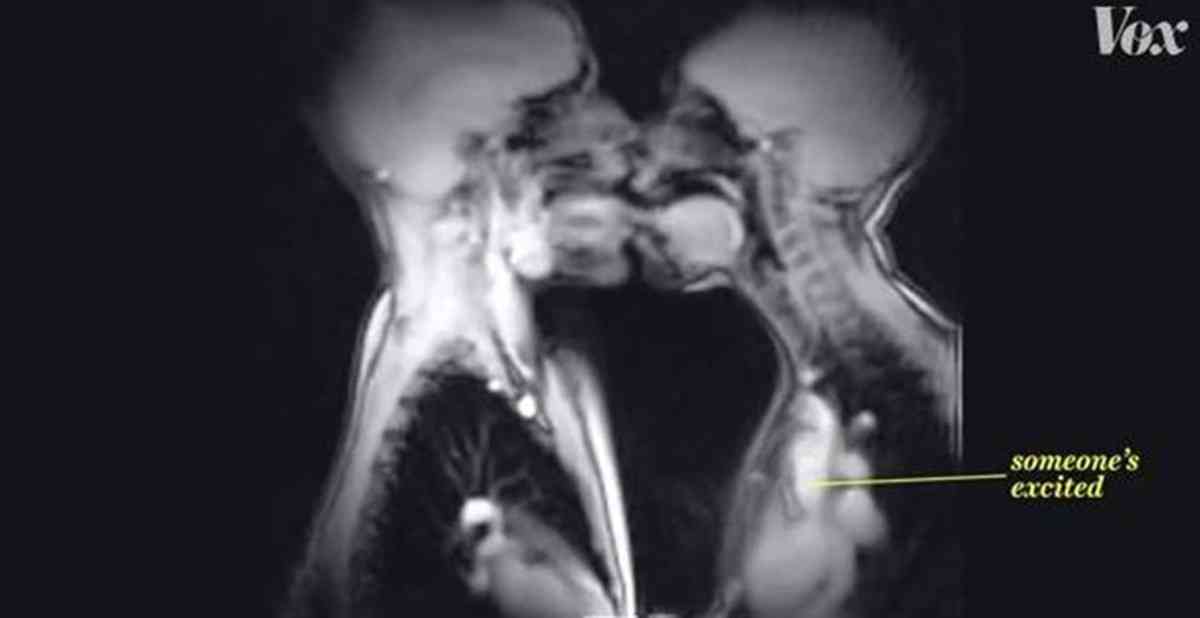

Οι εσωτερικές αντιδράσεις στη σεξουαλική επαφή (VIDEO) 27|09|2014 SCIENCE Δείτε ένα ενδιαφέρον βίντεο που κυκλοφόρησε πρόσφατα στο διαδίκτυο που δείχνει τις εσωτερικής αντιδράσεις του σώματος την ώρα της σεξουαλικής επαφής. Share it! TagsMRIvideo ΠΡΟΣΦΑΤΑ LIVING IN ATHENS Καταιγίδα στην Αθήνα σήμερα. Αναμένεται 3ήμερο ζέστης Βροχή άνω των 10 χιλιοστών στο κέντρο της Αθήνας 03|10|2025 LIVING IN ATHENS 1566: Η υγεία δεν μπορεί να είναι πολυφωνική. Γι’ αυτό τώρα γίνεται πολυκαναλική. Η ταινία για το 1566 και 1566.gov.gr καθρεφτίζει με υπερβολή αλλά και με χιούμορ την καθημερινή πραγματικότητα 03|10|2025 LIVING IN ATHENS Στην Αθήνα για πρώτη φορά το DOTS International Documentary Film Festival Θα προβληθούν 36 ταινίες ντοκιμαντέρ μικρού μήκους από 15 διαφορετικές χώρες, όλες με κεντρικό θέμα τον άνθρωπο. 03|10|2025 LIVING IN ATHENS Αθήνα, Νέα Εποχή Τουριστικής Ανάπτυξης και Επενδύσεων Αυτόνομος τουριστικός προορισμός η πρωτεύουσα Η Αθήνα επανακάμπτει δυναμικά στον τουριστικό χάρτη, αφήνοντας πίσω... 18|07|2025 LIVING IN ATHENS Η φωνή των γυναικών στην Αθήνα Χάρης Δούκας: «Δίνουμε βήμα στη φωνή των γυναικών» 18|07|2025 THE CITIZEN Zagori Mountain Running 2025 18,19 & 20 Ιουνίου Ο μεγαλύτερος αγώνας ορεινού τρεξίματος, το Zagori Mountain Running, επιστρέφει στις 18, 19 και 20 Ιουνίου ανανεωμένος με... 11|06|2025 ΣΧΕΤΙΚΑ ΑΡΘΡΑ LIVING IN ATHENS Καταιγίδα στην Αθήνα σήμερα. Αναμένεται 3ήμερο ζέστης Βροχή άνω των 10 χιλιοστών στο κέντρο της Αθήνας 03|10|2025 LIVING IN ATHENS 1566: Η υγεία δεν μπορεί να είναι πολυφωνική. Γι’ αυτό τώρα γίνεται πολυκαναλική. Η ταινία για το 1566 και 1566.gov.gr καθρεφτίζει με υπερβολή αλλά και με χιούμορ την καθημερινή πραγματικότητα 03|10|2025 LIVING IN ATHENS Στην Αθήνα για πρώτη φορά το DOTS International Documentary Film Festival Θα προβληθούν 36 ταινίες ντοκιμαντέρ μικρού μήκους από 15 διαφορετικές χώρες, όλες με κεντρικό θέμα τον άνθρωπο. 03|10|2025 LIVING IN ATHENS Αθήνα, Νέα Εποχή Τουριστικής Ανάπτυξης και Επενδύσεων Αυτόνομος τουριστικός προορισμός η πρωτεύουσα Η Αθήνα επανακάμπτει δυναμικά στον τουριστικό χάρτη, αφήνοντας πίσω... 18|07|2025 LIVING IN ATHENS Η φωνή των γυναικών στην Αθήνα Χάρης Δούκας: «Δίνουμε βήμα στη φωνή των γυναικών» 18|07|2025 THE CITIZEN Zagori Mountain Running 2025 18,19 & 20 Ιουνίου Ο μεγαλύτερος αγώνας ορεινού τρεξίματος, το Zagori Mountain Running, επιστρέφει στις 18, 19 και 20 Ιουνίου ανανεωμένος με... 11|06|2025